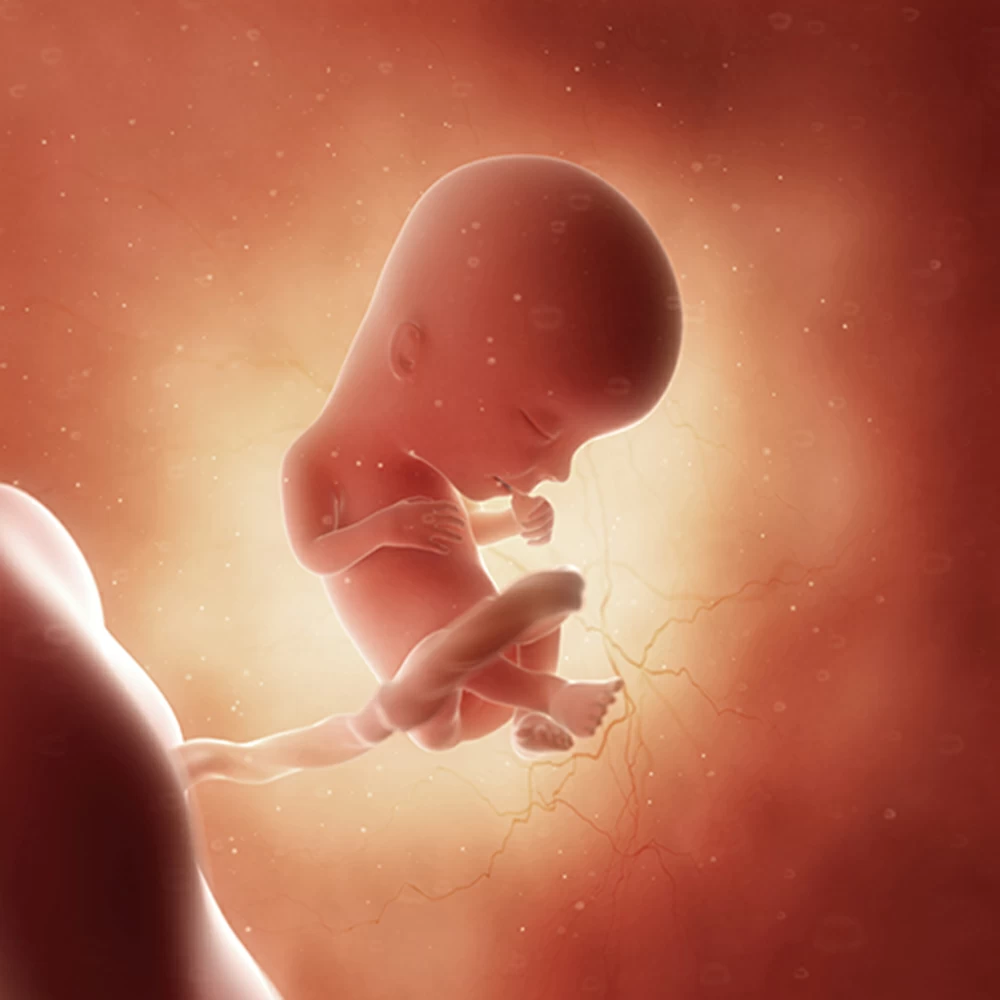

Неделя № 8

Тело эмбриона начинает выпрямляться, длина от темени до копчика составляет 15 мм в начале недели и 20-21 мм на 56 день, лицо ребенка становится привычным для человека: хорошо выражены глаза, прикрытые веками, нос, ушные раковины, заканчивается формирование губ.Отмечается интенсивный рост головы, верхних и нижних конечностей, начинается окостенение длинных костей рук и ног и черепа. Хорошо заметны пальцы. Восьмой неделей заканчивается эмбриональный период развития. Зародыш с этого времени называется плодом.